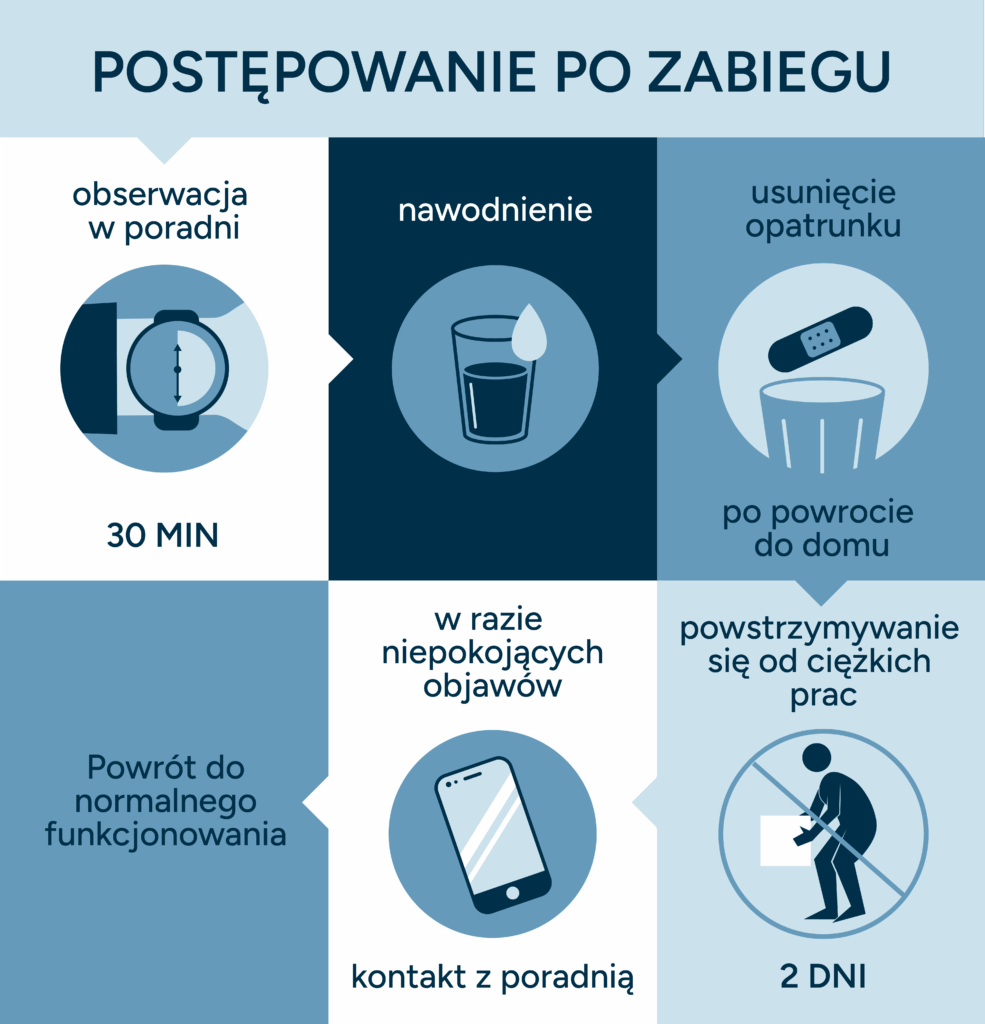

Po zabiegu pacjent może odczuwać niewielki ból w miejscu wkłucia, który zazwyczaj ustępuje po kilku godzinach. Zaleca się odpoczynek i unikanie nadmiernego wysiłku przez kilka dni. Efekt przeciwbólowy leku może wystąpić po kilku dniach i utrzymywać się przez różny czas, w zależności od rodzaju leku oraz indywidualnej reakcji pacjenta.